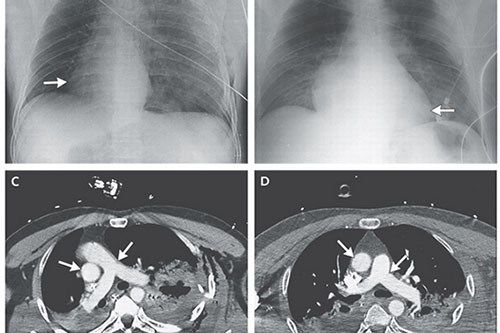

A motorcycle accident in Italy caused a man's heart to rotate within his body, and end up in the right side of his chest - a very traumatic injury from which he survived, according to a new report of his case. Doctors at the emergency department who treated the 48-year-old man discovered that his heart was in an unusual place when they tried to listen to his heart sounds and rhythms. An X-ray and CT scan of the man's chest showed that his heart had turned 90 degrees to the right, the doctors wrote in the report, published in the New England Journal of Medicine. "This is a very interesting anatomical finding, and it's very unusual," said Dr. Gregory Fontana, chairman of the department of cardiothoracic surgery at Lenox Hill Hospital in New York City, who wasn't involved in the case.